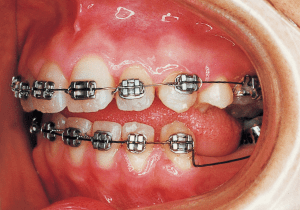

7 3-10-’86 Treatment Progress

Assessment and Management: Based on the pre-treatment condition (as assessed using models), the overjet and Class II molar relationship can be improved within the scope achievable by utilizing space created by extracting the maxillary left and right first premolars. Therefore, the treatment plan regarding tooth extraction would likely have been the same as that of the previous orthodontist. However, the progress of treatment over the past 10 months has not been entirely positive. Although it is unclear how these undesirable conditions arose, I determined they resulted from the destruction of the fixation and the influence of the tongue. I decided to continue treatment as is by rebuilding the mechanism.

The treatment progressed more favorably than anticipated, with the open bite and Class II malocclusion nearly resolved within five months of treatment initiation. However, discontinuing the use of rubber bands often resulted in an open bite.